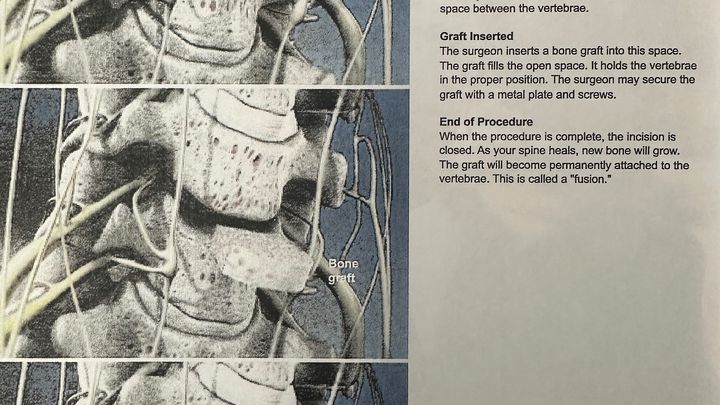

For over a year, I've had a pain in my neck and right shoulder blade. I thought I pulled something. Fast forward to May of this year. X-rays showed a narrowing of my cervical spine. I was sent to physical therapy. After 8 weeks of no relief, the PT recommended I have a follow-up appointment with my primary provider. Then they ordered an MRI. The results showed nerve damage caused by the degeneration of my C6-C7. I was then referred to a neurosurgeon at Bronson Methodist. The neurosurgeon recommended a fusion surgery that will most definitely help me. My surgery is scheduled for October 7.